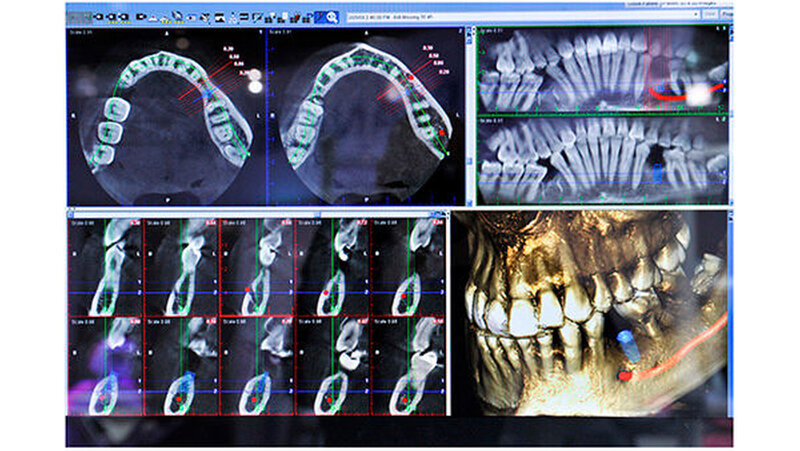

Für jeden dieser Prozesse stehen heute mehrere Wege zur Bohrschablone offen. Einer davon führt über zentrale Dienstleister: Der Zahnarzt schickt seine Planungsdaten und die 3-D-Röntgenaufnahme dorthin und bekommt nach einigen Tagen die entsprechende Bohrschablone retour. Alternativ dazu kann sie über eine praxis- oder laborseitige Schleifeinheit im eigenen Hause und ohne Zeitverzögerung hergestellt werden.Die höherwertigen 3-D-Systeme, im hohen fünfstelligen oder sechsstelligen Euro-Bereich, weisen einen größeren Scan-Bereich auf. Dies öffnet die Tür zu Ganzkieferaufnahmen inklusive Kiefergelenk - ideal bei Kieferfrakturen, bei Dysgnathien oder bei der Behandlung der craniomandibulären Dysfunktion.

Entscheidend wirkt sich auch hier aus, was als Software dazukommt: Zum Beispiel lässt sich mit digitalen Kieferbogensystemen die Bewegung des Kiefergelenks nachverfolgen. Dazu gibt der Diagnostiker dem Patienten bestimmte Anweisungen, wie er seinen Unterkiefer bewegen soll. Die daraus gewonnenen Bewegungsinformationen helfen in Kombination mit statischen 3-D-Röntgenbildern zum Beispiel bei der Schienenherstellung.